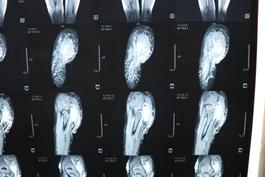

经过检查发现小诺右侧臀部及大腿有大面积的淋巴畸形,右小腿、右足踝部及右足底也有许多弥散性的肿块,不仅病变部位多且侵犯严重,加上之前已经做过三次手术,这次的手术对于医生而言无疑是巨大的挑战!经过前期充分的准备,小诺的手术如期进行,从上午10点50一直到晚上11点,历时整整12个小时,终于顺利完成手术,术中发现病变累及大面积的正常肌肉和多处神经,乔主任巧妙的采用切除和微创相结合的方式治疗病变部位,仔细分离重要的血管和神经,将大面积的病变全都切除。术后小诺身体恢复情况很好,目前正在一步步的康复,迎接她的是健康和快乐的明天!